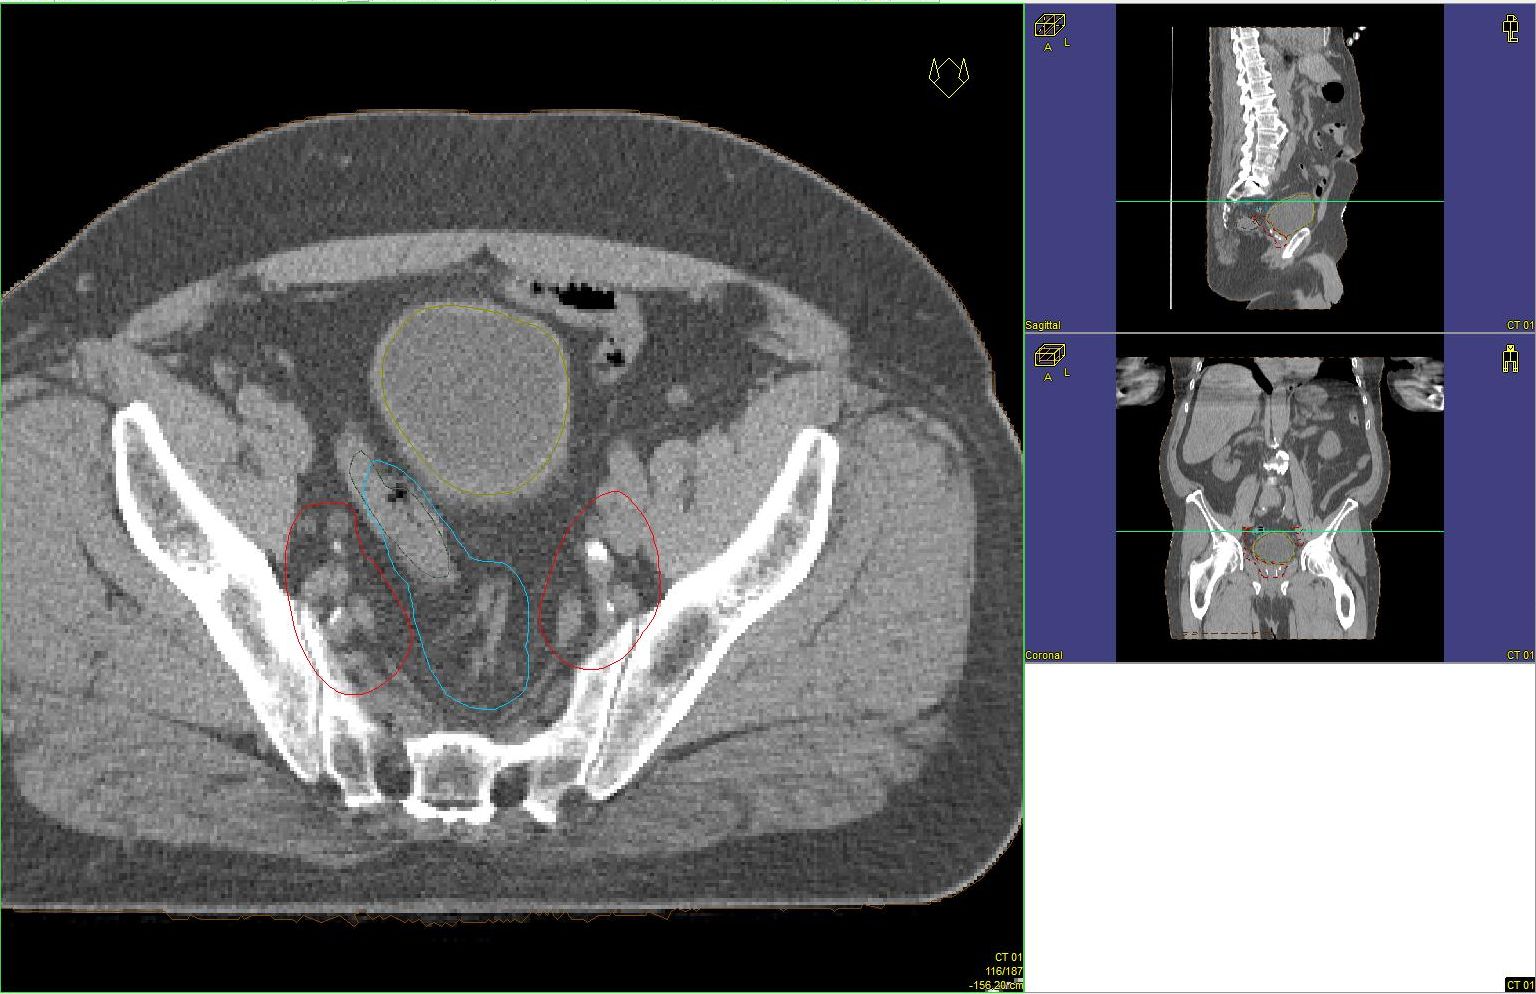

Prostata-Ca: Zielvolumen der postoperativen Radiotherapie

Beispiel: postoperative RT